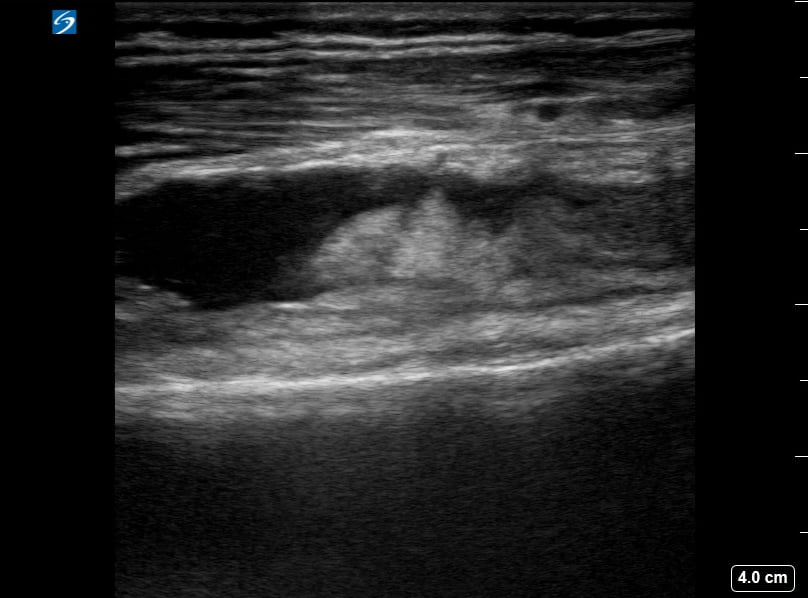

Knee effusion, in musculoskeletal (MSK) ultrasound, refers to the abnormal accumulation of fluid within the knee joint capsule. This common medical finding can indicate various pathologies, including trauma, inflammation (like arthritis), or infection. Ultrasound is a highly effective tool for detecting and quantifying knee effusions, allowing clinicians to assess fluid volume, characterize its nature (e.g., anechoic, complex), and guide aspiration procedures for diagnostic or therapeutic purposes.

Accurate identification of knee effusion via ultrasound is crucial for guiding patient management in sports medicine and orthopedics. Its real-time capabilities and portability make it an indispensable imaging modality for rapid diagnosis and monitoring of joint conditions, aiding in precise medical interventions and optimizing patient outcomes.